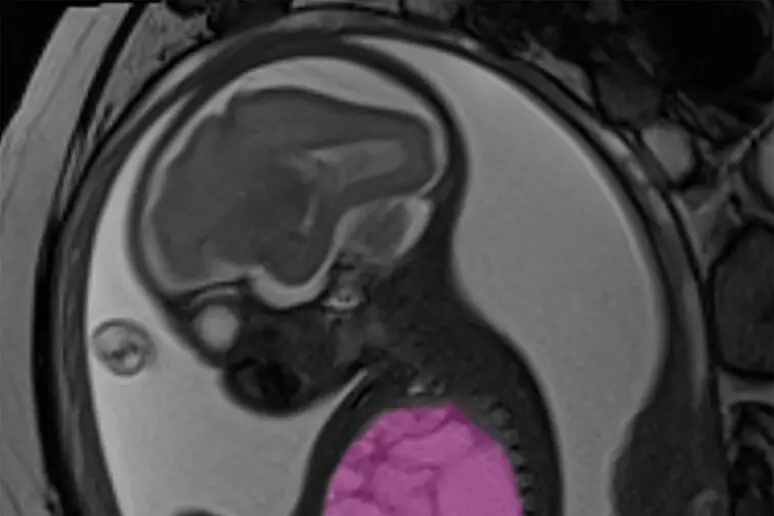

Roma – È una storia a lieto fine quella del piccolo Alessandro (nome di fantasia), salvato grazie a un intervento complesso eseguito quando era ancora nel grembo materno. La cisti polmonare, grande come un’arancia, comprimeva cuore e polmoni, provocando un grave scompenso cardiaco fetale e mettendo a rischio la sua sopravvivenza.

L’intervento in utero è stato realizzato dall’équipe di chirurgia fetale dell’ospedale pediatrico Bambino Gesù di Roma, in collaborazione con i ginecologi dell’ospedale San Pietro Fatebenefratelli, durante la 24esima settimana di gestazione. I chirurghi hanno posizionato uno shunt pleuro-amniotico, un sottile drenaggio che mette in comunicazione il torace del feto con il liquido amniotico, ristabilendo la normale funzione cardiaca.

Alessandro è poi nato tramite cesareo programmato alla 35esima settimana. Subito dopo la nascita, i neonatologi del Bambino Gesù hanno confermato la presenza della cisti nel polmone destro e, il giorno successivo, i chirurghi neonatali hanno eseguito una lobectomia toracoscopica, rimuovendo il lobo inferiore malato con una tecnica mini-invasiva.